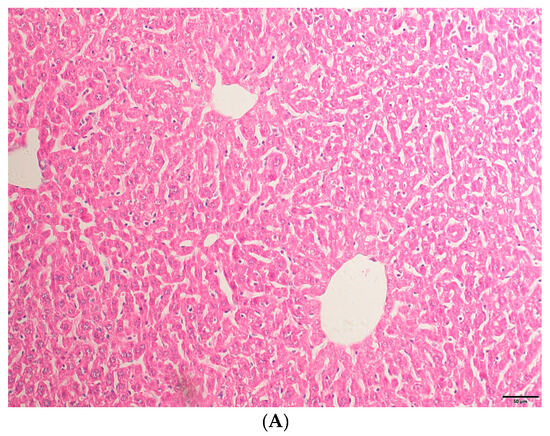

2.1. HE Staining Results